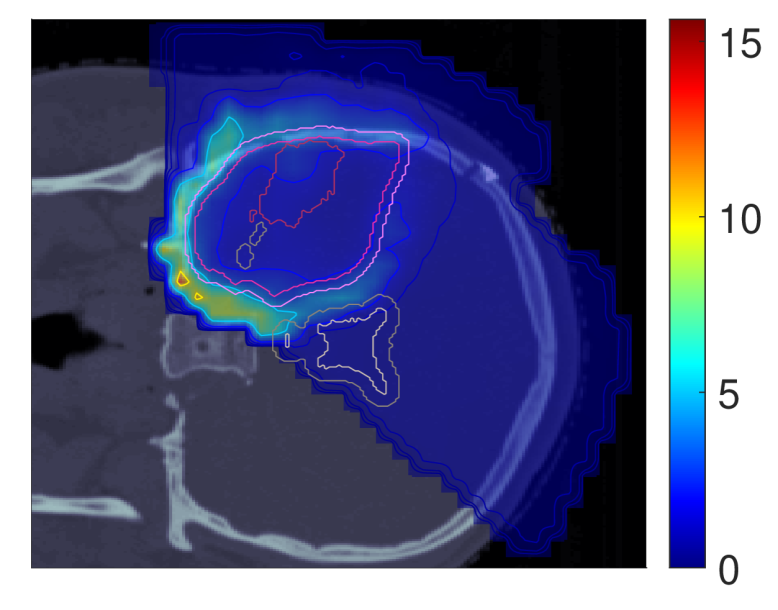

In light of the dose distribution changes and the interdependency between dose and dose-averaged LET, we can identify patterns in the slice images with the optimal dose-averaged LET distributions shown in Figure 5.

NTCP30 %NTCP\approx{$30\text{\,}\mathrm{\char 37\relax}$} NTCP20 %NTCP\approx{$20\text{\,}\mathrm{\char 37\relax}$} NTCP10 %NTCP\approx{$10\text{\,}\mathrm{\char 37\relax}$}

Figure 5: Optimal slice images of the dose-averaged linear energy transfer ldl_{d} (in keV/μ\boldsymbol{\mu}m) for NTCPpNTCP_{p}, LSEp~LSE_{\tilde{p}}, H~p\tilde{H}_{p} and H~p~\tilde{H}_{\tilde{p}} at different NTCP levels. The shifts in ldl_{d} coincide with those observed on the slice images for dRBE,fxd_{RBE,fx}, i.e., there seems to be a trade-off between dRBE,fxd_{RBE,fx} and ldl_{d} that is consistent with the mathematical structure of the POLO model. As a result, the ldl_{d} slice images for NTCPpNTCP_{p} and H~p\tilde{H}_{p} are almost equivalent, while LSEp~LSE_{\tilde{p}} and H~p~\tilde{H}_{\tilde{p}} differ. For the latter two objective functions, the shift of dRBE,fxd_{RBE,fx} outside the target volume appears to be crucial, or, respectively, no shift of ldl_{d} is necessary due to the strength of the reduction of dRBE,fxd_{RBE,fx}.

First, we note that ldl_{d} hotspots do not manifest in the high dose regions – this would be a risk driver because of the product term in the POLO model from Section II.A. Generally, some trade-off between dRBE,fxd_{RBE,fx} and ldl_{d} is evident, where the optimizer allows for higher values of ldl_{d} when dRBE,fxd_{RBE,fx} has been sufficiently reduced, and vice versa.

For NTCPpNTCP_{p}, the slight reduction of dRBE,fxd_{RBE,fx} outside the target volume coincides with a redistribution of ldl_{d}: higher values in the target volume are prevented, and instead induced along the margins of the PTV. Once again, H~p\tilde{H}_{p} behaves almost identically. Following the dose/LET trade-off, the almost unchanged values for LSEp~LSE_{\tilde{p}} can also be explained: LSEp~LSE_{\tilde{p}} minimally reduces dRBE,fxd_{RBE,fx} in the region of overlap with the VS, meaning that high ldl_{d} values there would be detrimental to the outcome prediction. Consequently, ldl_{d} could only approach the “dose gap” that opens up within the target volume, or remain constant while the shifts in the dose distribution account for the reduction in NTCP.

Finally, for H~p~\tilde{H}_{\tilde{p}}, we observe a sharp envelopment of the lower side of the PTV margin, consistent with the fall-off in dRBE,fxd_{RBE,fx} there. At an NTCP level of 10 %10\text{\,}\mathrm{\char 37\relax}, the high ldl_{d} region has virtually manifested itself with hot spots partially overlapping the VS. However, revisiting the slice image for dRBE,fxd_{RBE,fx}, this is not surprising, as in addition to the lower values in the target volume, the dissipation of dRBE,fxd_{RBE,fx} to the outside is only enhanced towards the upper end, leaving space for the ldl_{d} band on the lower end, between the PTV margin and the VS.